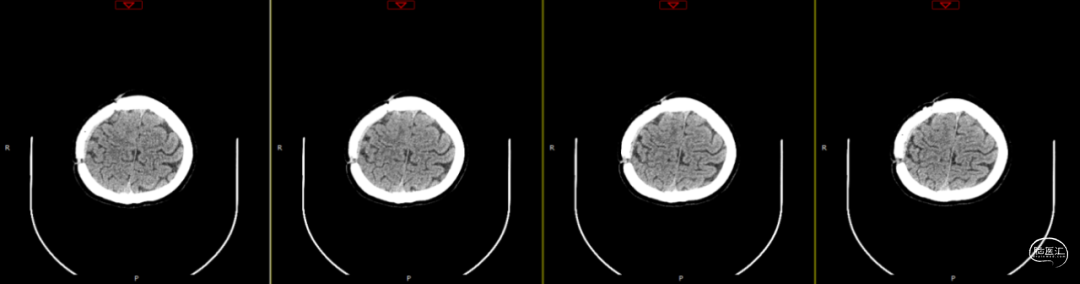

第2次手术后第17天,行颅脑CT检查(如上图),科室讨论仍建议去骨瓣清创,但患者情绪波动明显,拒绝去骨瓣;经协商后行硬膜外脓肿置管引流术。术中根据术前规划,切开颞顶部部分头皮,高速磨钻经骨缘与骨瓣之间磨出骨孔及骨槽,可见骨缘硬脑膜增生,深部硬膜增厚,并伴有灰黄色粘稠脓性液体流出,无明显异味,使用无菌注射器收集脓液约7ml,备细菌培养等检查;置引流管于硬膜外,骨瓣下,反复使用温生理盐水冲洗至水清晰,接负压吸引,及引流袋;术后继续使用万古霉素及美罗培南联合抗炎治疗。术后每日使用万古霉素溶液冲洗硬膜外腔1次。

第3次术后第9天复查颅脑CT(如上图)。

第3次术后16天,复查颅脑MRI(如上图),硬膜外及皮下异常信号较前明显减少,负压引流管引流不明显,拔除负压引流管,继续使用头孢曲松+多西环素口服联合抗炎治疗。

第3次术后23天,拔管后7天复查颅脑(如上图)。

第3次手术后49天,出院后2周复查颅脑CT情况(如上图),刀口愈合正常,患者回归日常生活、学习。